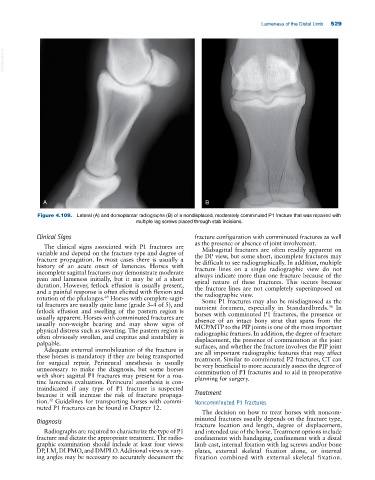

Figure 4.109. Lateral (A) and dorsoplantar radiographs (B) of a nondisplaced, moderately comminuted P1 fracture that was repaired with

multiple lag screws placed through stab incisions.